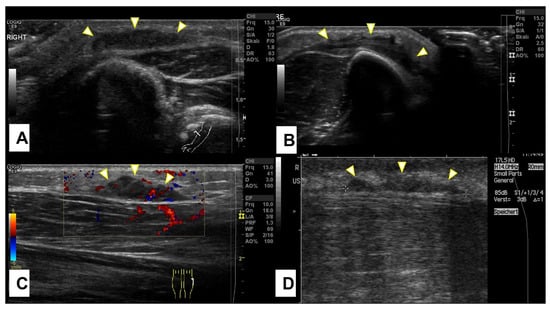

All SGA patients received an ultrasound examination (US) at their first encounter. On the US, SGA were described as nonspecific mass(es) with interacting hypo- and hyper-echoic zones, ill-defined borders, and mild hypervascularization (Figure 4).

Figure 4.

Representative slices of ultrasound imaging of subcutaneous granuloma annulare (SGA). The lesions are strictly epifascial with hypo- and hyper-echogenic zones and mild hypervascularization. A common finding is the cap shape of these lesions, marked with arrowheads. The depicted lesions were located on (A) the right forearm; (B) the right lower leg; (C) the left lower leg; (D) the right lower leg.

On ultrasound, an SGA appears as an epifascial subcutaneous soft tissue mass, hypoechogenic in the center, with a hyperechoic zone in the periphery and mild vascularization. This lesion projects over the surface of the muscle’s fascia without invading it. Supposing that during the ultrasound evaluation, it is possible to recognize the epifascial cape shape of the lesion, we recommend using SGA as your primary working diagnosis and referring the child for a clinical follow-up with a repeat US of the lump in 4 weeks (Figure 12).